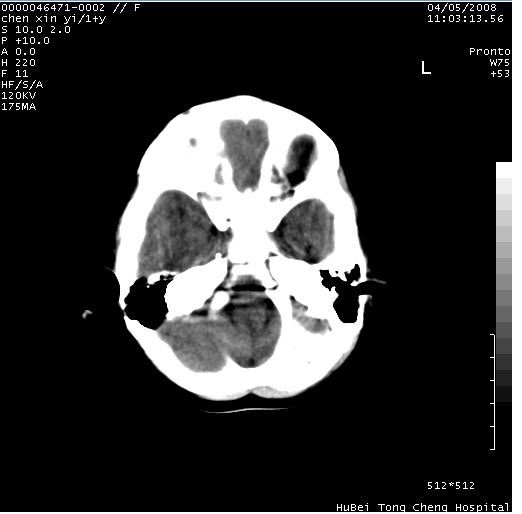

以下是引用zhangzhongshou在2008-4-9 12:54:00的发言:[br]请结合病史,有以下可能1、炎性肉芽肿钙化(含结核)2、寄生虫钙化(含脑囊虫)3、其他良性钙化性病变